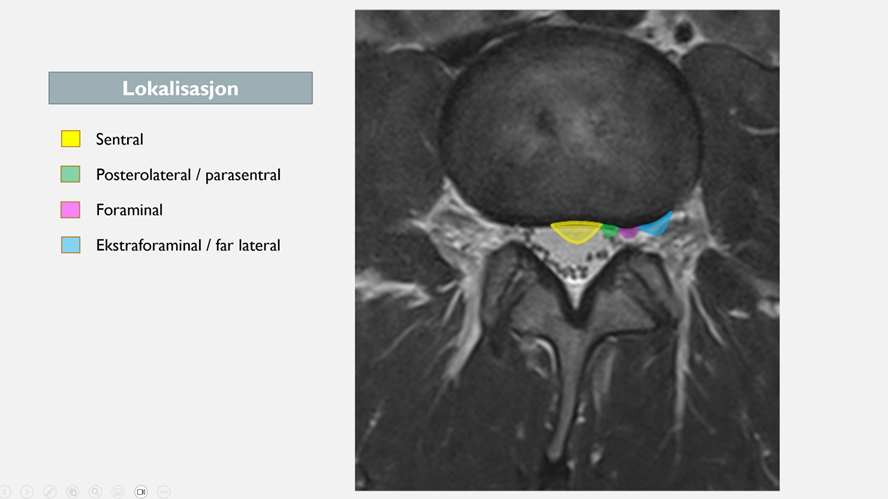

Hvor prolapsen sitter kan være avgjørende for plager og om det er radikulær smerte. Det vanligste er å dele inn på følgende måte:

1. Sentral

En sentral prolaps er bedre, og gir sjeldnere radikulopati (hvis det ikke er en stor prolaps = cauda equina). Nerven har større sjanse for å komme unna! Det er lite sannsynlig at en liten sentral prolaps (protrusjon) vil gi veldig mye plager, og det er sjeldnere at en ekstrusjon gir noe langvarig radikulær smerte – utover den kjemiske irritasjonen i starten.

2. Posterolateral/parasentral prolaps

Har du en pasient med prolaps og radikulopati er det mest sannsynlig parasentral lokalisasjon. Over 3/4 av skiveprolapsene skjer parasentralt (2). I dette området er annulus fibrosus tynnere og mangler støtte fra ligamentum longitudinale posterius. Det er kort vei til nerverot (25). Nesten alle lumbale prolapser skjer i L4/5 og L5/S1, dermed sannsynlig at L5 eller S1-nerverot er affisert.

3. Foraminal/far lateral prolaps

Du kan ha pasienter med bensmerter, negativ SLR/lasegue, som fortsatt kan ha prolaps med sterke radikulære smerter. Disse kan ha en foraminal prolaps.

De foraminale og ekstraforaminale skiveprolapser er sjeldnere (7-12 % / 21 %) enn de sentrale og parasentrale (26). Disse prolapsene kan påvirke nerverot på samme nivå der den går ut i foramen intervertebrale. Disse pasientene kan ha et sterkere symptombilde, da skivemateriale kan trenge ut i en trangere kanal med begrenset plass til forskyvning av nerven. Spinalganglion til bakre horn befinner seg også her, som også er en potensielt smertesensitiv struktur (27,28). En studie bekrefter dette, da disse pasientene hadde mer radierende bensmerter sammenlignet med sentrale og parasentrale skiveprolapser (26).